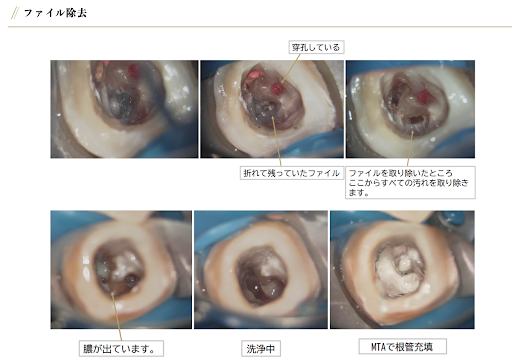

根管治療の症例紹介

治療名

根管治療

治療説明

歯茎が腫れてなかなか治らないと来院されました。

根管内に残っていたファイルや根充材を取り除くと膿が出てきました。

徹底的に洗浄し、排膿が止まった時点でMTAにて根管充填し終了しました。

治療回数・期間

治療回数:2~4回/治療期間:2週間

副作用とリスク

この治療で症状が治まらない場合は外科的な治療が必要です。